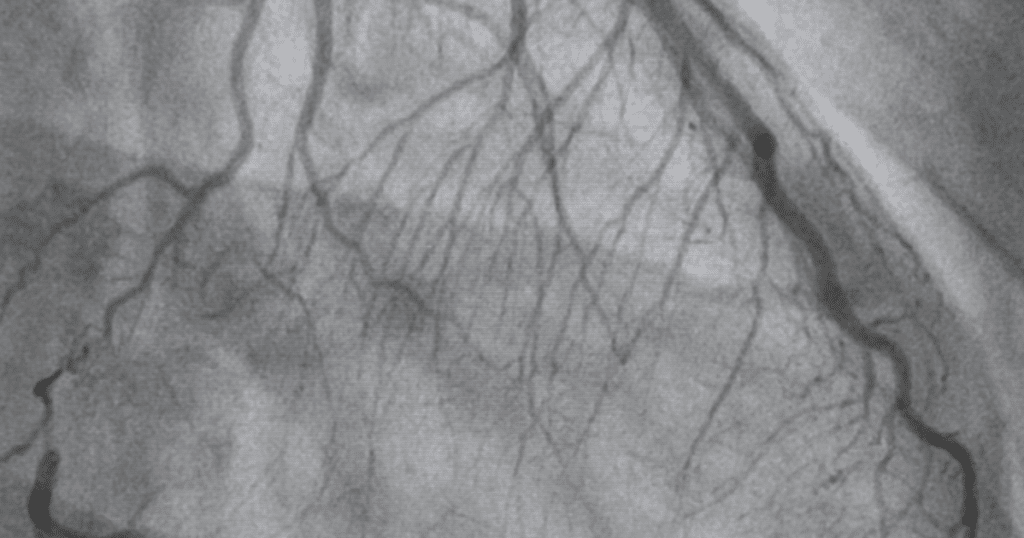

By combining high-resolution CT technology with an intravenous contrast agent, CTCA produces detailed 3D images of the heart vessels, allowing precise evaluation of blockages, vessel narrowing, plaque burden, and calcium deposits-often before symptoms become severe.

During the procedure, contrast dye is administered through a peripheral vein, while a high-speed CT scanner captures images synchronized with the cardiac cycle.

This advanced timing significantly reduces motion artifacts and ensures clear visualization of even small coronary branches.

CT Coronary Angiography and conventional angiography differ primarily in approach and clinical use. CTCA is non-invasive, requires no catheter insertion, and is ideal for ruling out coronary artery disease in low- to intermediate-risk patients.

In contrast, conventional angiography is an invasive procedure typically reserved for cases where immediate intervention, such as angioplasty or stenting, is required. Therefore, CTCA is often recommended as a first-line diagnostic tool, helping clinicians avoid unnecessary invasive procedures while ensuring accurate cardiac assessment.